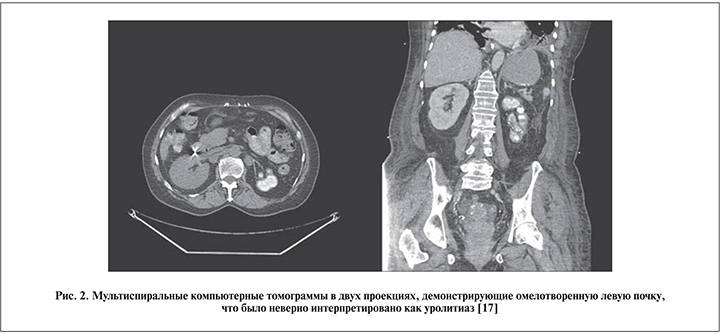

Второй пример – также пожилая 70-летняя канадка греческого происхождения, которая была оперирована по поводу коралловидного камня вторично сморщенной почки. Тридцать лет назад ей была выполнена илеоцистопластика по поводу сморщенного мочевого пузыря, который выявили во время лечения туберкулеза легких. Совершенно очевидно, что в то время у нее был и туберкулез почек, поскольку туберкулез мочевого пузыря всегда вторичен по отношению к нефротуберкулезу, но почему-то диагностирован не был. В результате погибшая почка имбибировалась солями кальция (так называемая аутоампутация почки), но это исход нефротуберкулеза, а не сопутствующая мочекаменная болезнь (рис. 2).